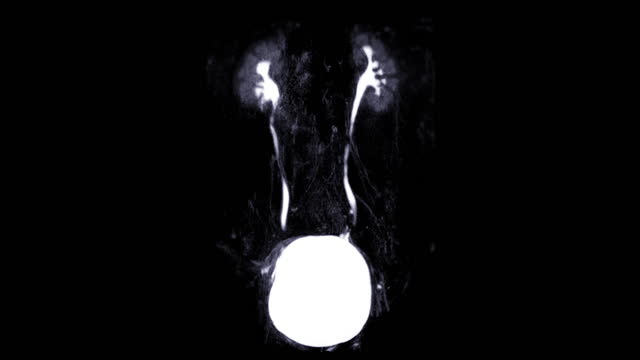

- 영상 검사를 통해 신장의 이상을 확인합니다. CT 스캔, MRI, 혹은 초음파 등의 영상검사를 통해 신장암의 덩어리를 확인할 수 있습니다.